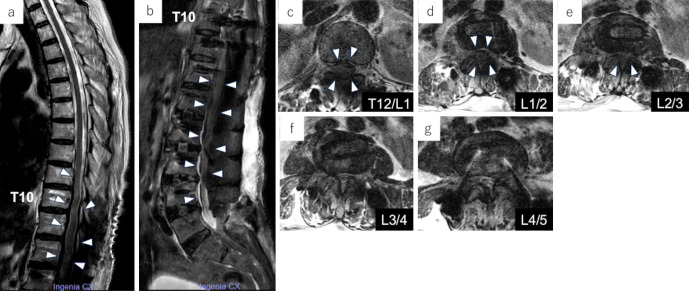

Spinal Subarachnoid Hemorrhage as a Very Rare Complication Following Circumferential Minimally Invasive Surgery Using Lateral Interbody Fusion and Percutaneous Pedicle Screw Fixation for Adult Spinal Deformity.

经皮椎弓根螺钉经外侧椎体间融合术治疗成人脊柱畸形后,椎蛛网膜下腔出血是非常罕见的并发症。